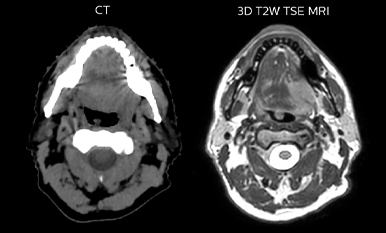

Comparison of CT simulation scan

Comparison of CT simulation scan (left) and T2W 3D MRI (right)

While CT clearly defines bone and cartilage, the modality’s limited soft tissue visualization makes head-and-neck structures often appear virtually indistinguishable from another. Coregistering an MRI dataset as a secondary information source for head-and-neck target and organ at risk (OAR) delineation is vital, according to La Tour’s Dr. Breuneval.

“MRI contributes substantially to visualizing head-and-neck lesions compared to CT and allows a better differentiation of normal from abnormal tissue,” he explains. “Tumor edges and extracapsular lymph node extension – as well as OARs, such as parotid glands, pharyngeal muscles and the brachial plexus – are better depicted. The resulting benefit is that tumor margins may be reduced and OARs better spared.”